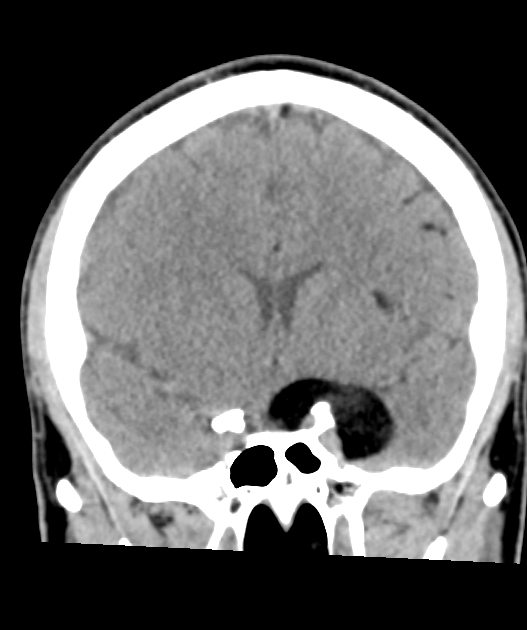

- A 30-year-old patient presented with an acute onset headache.

- MRI showed a lesion in the right cavernous sinus that was T1-hyperintense that suppressed on the fat-suppressed FLAIR imaging, consistent with fat content.

- There were further locules of fat signal over the cerebral hemispheres consistent with dermoid cyst rupture.

- CT:

- Fat-fluid levels

- Calcification

- Fat attenuation within lesion (-20 to -120 HU)